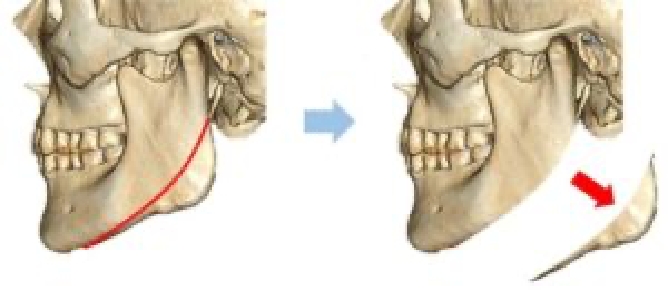

骨切り量が非常に大きい

オトガイ神経を剥離して下顎骨を広範囲に露出し、神経の上下からアプローチするため、骨切り範囲がオトガイ部先端から下顎角直前におよび、切除幅8㎝~10㎝、全長14cm~16cmと非常に大きい。

スムーズなカーブラインの

骨切りが可能

骨切りカッターを垂直に骨に当てるため、下顎角直前までスムーズなカーブラインの骨切りが可能。

希望に応じた

Vラインのオトガイ形成

オトガイ部先端から下顎角直前までの広い範囲の骨切りによってシャープなVライン形成が可能。